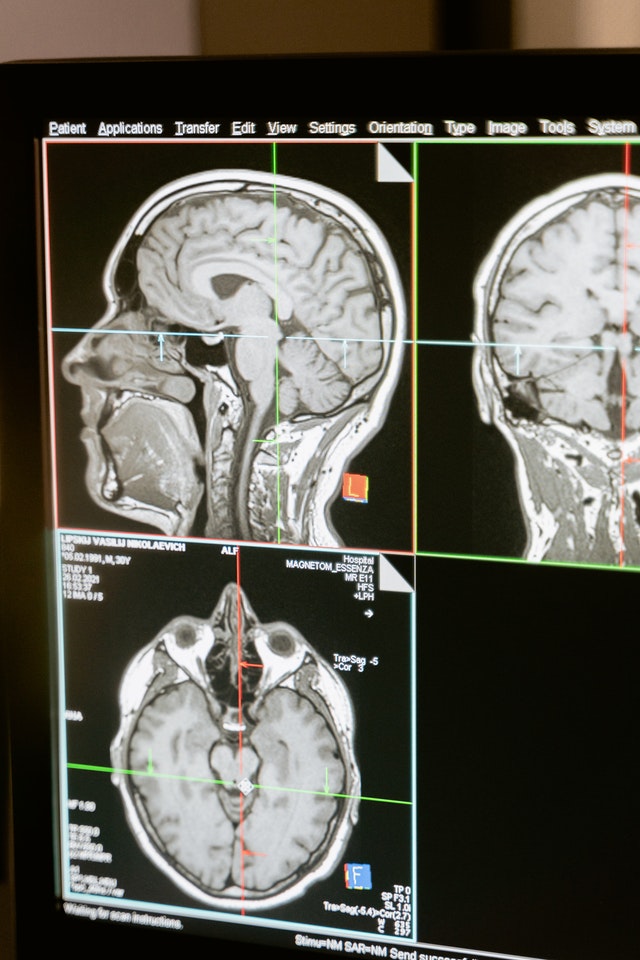

Medipol Mega Üniversite Hastanesi Fiziksel Tıp ve Rehabilitasyon Bölümü’nden Doç. Dr. Didem Sezgin Özcan, genç yaşta da görülebilen inmeye ilişkin yaptığı açıklamada, felç olarak da bilinen inmenin, damar tıkanıklığı (iskemi) ya da kanama (hemoraji) sonucu ortaya çıkabildiğini belirtti.

Doç. Dr. Özcan, inmenin, beyni besleyen damarlardan birinin kan akımının azalması ya da kesintiye uğramasıyla ilişkili olduğunu ifade ederek, "Beyin dokusunda hasar oluşması sonucu beyin fonksiyonlarında aniden gelişen kısmi kayıplarla karakterize bir tablodur. Beyinde gerçekleşen hasarın yerine ve şiddetine bağlı olarak her hastada farklılık gösteren belirtilere neden olur.